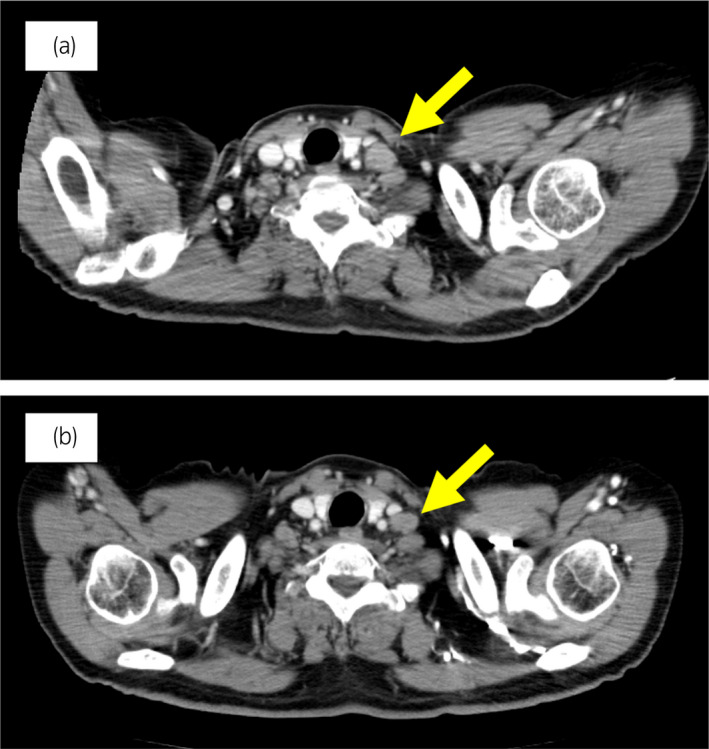

70 歲男性被診斷為轉(zhuǎn)移性 PC,cT3bN1M1b,Gleason 評(píng)分(GS)為 4 + 5 = 9,前列腺特異性抗原(PSA)水平為 40.8ng/ml,3 年前伴有胸椎轉(zhuǎn)移。 對(duì)前列腺進(jìn)行聯(lián)合雄激素阻斷 (CAB) 治療和質(zhì)子放射治療 (78.0Gy/39fr)。 PSA 水平降至 <0.01ng/ml,CAB 在 2.5 年后停止。 停止 CAB 五個(gè)月后,他出現(xiàn)背痛,PSA <0.01 ng/ml。 計(jì)算機(jī)斷層掃描 (CT) 掃描檢測(cè)到多處肝、骨和淋巴結(jié)轉(zhuǎn)移,神經(jīng)元特異性烯醇化酶 (NSE) 水平高達(dá) 171ng/ml(圖 1a)。 骨轉(zhuǎn)移活檢顯示神經(jīng)內(nèi)分泌前列腺癌 (NEPC) 的診斷(圖 2),患者被轉(zhuǎn)診至佳學(xué)基因合作醫(yī)院。 內(nèi)分泌腫瘤正確治療醫(yī)生用順鉑、依托泊苷和亮丙瑞林治療。 第三個(gè)療程后,轉(zhuǎn)移部位明顯縮?。▓D 1b)。 順鉑和依托泊苷治療 1 年,但患者因神經(jīng)病變要求停藥。 他開(kāi)始服用恩雜魯胺。 治療 3 個(gè)月后,患者出現(xiàn)背痛和左鎖骨下淋巴結(jié)腫大(圖 3a)。 肝轉(zhuǎn)移保持不變,順鉑治療后縮小。 通過(guò)腫瘤正確用藥850基因檢測(cè)證實(shí)了 BRCA2 突變。根據(jù)基因檢測(cè)結(jié)果,主治腫瘤科醫(yī)生給予了奧拉帕尼。 三個(gè)月后,背痛好轉(zhuǎn),淋巴結(jié)轉(zhuǎn)移縮小,確定為部分緩解(PR)(圖3b)。 肝轉(zhuǎn)移灶保持不變。

圖 3:案例 1. 開(kāi)始使用奧拉帕尼之前和之后 3個(gè)月的鎖骨下淋巴結(jié)轉(zhuǎn)移的 CT 圖像。 (a) 治療前和 (b) 奧拉帕尼治療后 3 個(gè)月。 黃色箭頭顯示轉(zhuǎn)移淋巴結(jié)。